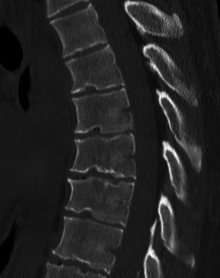

Scheuermann's disease is a self-limiting skeletal disorder of childhood. Scheuermann's disease describes a condition where the vertebrae grow unevenly with respect to the sagittal plane; that is, the posterior angle is often greater than the anterior. This uneven growth results in the signature "wedging" shape of the vertebrae, causing kyphosis. It is named after Holger Werfel Scheuermann.[1][2][3]

Diagnosis is typically by medical imaging.